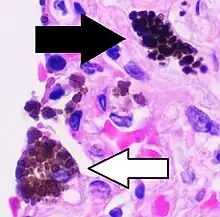

![]() Cytology of a macrophage with typical features. Wright stain. | |